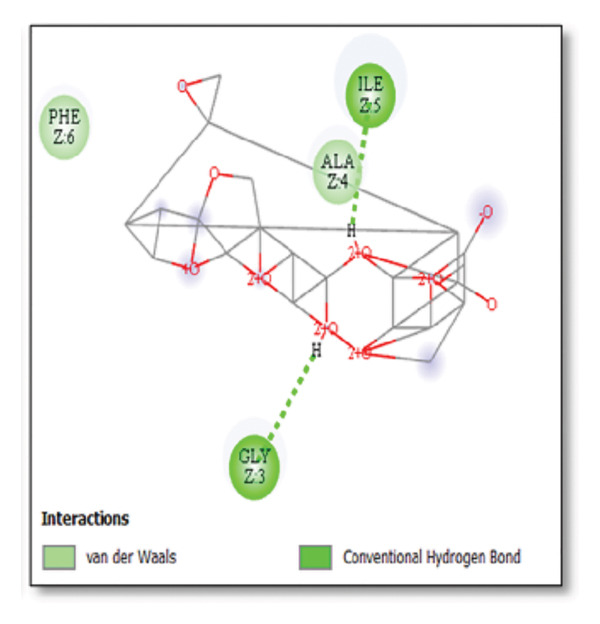

Against the core Aβ peptide, ginkgolide again showed the lowest binding energy (−8.40 kcal/mol), though no direct hydrogen bond interactions were detected in the lowest‐energy pose. Ginsenosides (−4.36 kcal/mol) demonstrated stable interactions, notably forming H‐bonds with ALA4 and LYS2.

Ginsenosides (−4.36 kcal/mol) formed a highly optimal bond with ALA4 (carbonyl oxygen [O] donor) with a short distance (2.56 Ǻ) and a near line angle (160.82°). Cyanidin (−3.94 kcal/mol) also formed H‐bonds with ILE5 and ASN1. The reference drug memantine exhibited significant binding at −3.56 kcal/mol, forming an H‐bond with the critical amyloidogenic residue ILE5 D‐A 2.80 Ǻ, angle: 159.52°. Figure 4 summarizes the binding characteristics for Aβ peptide.

Similarly, interactions with the clusterin receptor (also known as ApoJ) were mediated through a crucial binding site involving PHE240. PHE240 is a key hydrophobic residue within clusterin’s large chaperone domain. Our findings suggest that ginsenosides use a hydrophobic interaction at this specific residue to modulate the chaperone activity, thereby potentially stabilizing clusterin in a conformation that effectively prevents $\text{A}\beta$ from forming toxic oligomers [ref. 46]. Aβ peptide ginsenosides were shown to interact directly with ALA4 and LYS2. These particular residues are located in a critical hydrophobic region of the Aβ peptide, which is essential for its initial self‐association and subsequent aggregation into neurotoxic oligomers and fibrils. The ginsenoside interaction at these sites provides a compelling direct mechanism for how these compounds could inhibit Aβ aggregation, a central pathological event in AD [ref. 47].